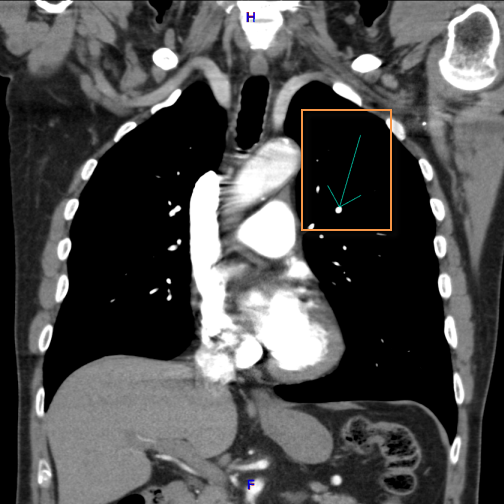

The Hounsfield annotation tool creates a region of interest and calculates its average pixel value and the standard deviation on the distribution.

To obtain a Houndsfield Value measurement:

Select the

Hounsfield Value  icon

icon

Click on the region of interest

Drag on the mouse to encircle the area

Release the mouse button

The default region of interest drawn on the image is a true circle. When resizing the ROI, maintain a true circle by using the corner grab points

The center grab point  will move ROI around the image and others will elongate

or narrow.

will move ROI around the image and others will elongate

or narrow.